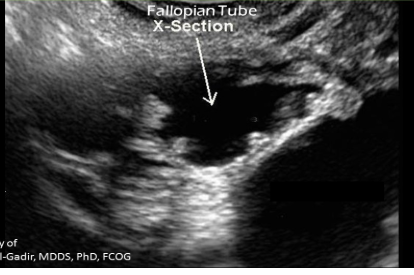

COGWHEEL SIGN - demonstrated in cross-sectional view, longitudinal folds of tube thicken

Hydrosalpinx/pyosalpinx, COGWHEEL

Acute PID (cogwheel)

Cogwheel sign indicated what stage of PID

Acute salpingitis